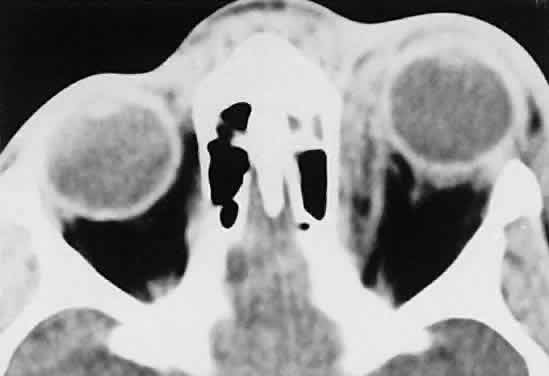

Sporadic North American cases have a less-definitive viral association. These patients differ clinically in their age of presentation (mean, 11 years) and in the usual site of tumor origin (intra-abdominal lymphoid tissue).40,41 Involvement of the facial bones and orbit is less common in the North American cases, but invasion of the orbit from the sinuses may occur42,43 (Fig. 4).

Fig. 4. Burkitt's lymphoma involving the posterior ethmoids, skull base, and both orbital apices in a 5-year-old boy.